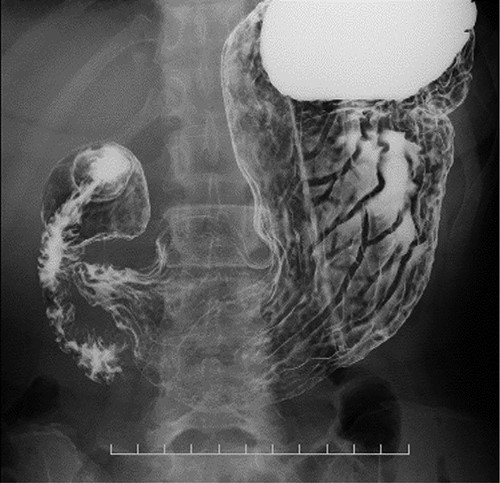

Esophagram findings; the esophagram shows stricture in the middle thoracic esophagus; a nasogastric tube could pass through the stenosis, and tube feeding was started.

A 48-year-old woman accidentally ingested an alkaline detergent and was transported to the emergency medical care center of a local hospital. Conservative treatment using a proton pump inhibitor and a mucosal protectant was initiated. Although this treatment was lifesaving, an esophageal stricture developed, and the patient developed dysphagia and gradually lost weight. Two months later, she was referred to our hospital for balloon dilatation. The esophageal stenosis was severe and >10 cm in length (Fig. 1); therefore, balloon dilatation was impossible. A nasogastric tube was inserted to improve the patient’s nutritional status. After 3 months, her nutritional status improved, and surgical treatment was deemed necessary.